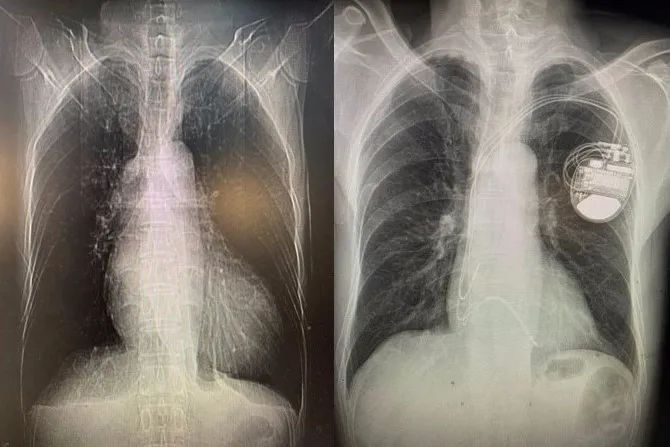

择日,孙冰主任医师和毛玉副主任医师所在的起搏团队为先生进行了起搏器植入手术。张先生植入的起搏器为三腔起搏器,共有三根导线经血管到达心脏,分别位于右心房、右心室和左束支。右心房、右心室得电极保证了心房心室收缩的同步性,并具有防治室速室颤的功能。而左束支电极可以纠正左束支传导阻滞,实现左室内部的收缩同步,改善心功能。经过精细定位和检测,左束支电极植入成功,起搏后可以看到张先生心电图的qrs波迅速变窄,标志左室收缩同步性的达峰时间和胸前导联qrs波移行也非常理想。手术很成功。术后心电图已经看不到原来宽宽的qrs波了,几乎与正常心电图完全一样。这意味着心脏电传导得到了改善,张先生的脸上也露出了笑容。

术前;术后